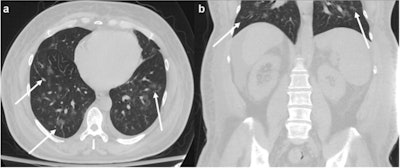

A 58-year-old male presenting with abdominal pain for seven days, who was subsequently discovered to be COVID-19 positive. (a) Axial and (b) coronal CT at the level of the lung bases show multifocal bilateral ground-glass opacities with a rounded morphology (arrows), many of which are peripheral in distribution. This patient was hospitalized and ultimately died 10 days later from respiratory failure related to COVID-19. Images and caption courtesy of European Radiology.The team sought to describe the clinical and lung CT findings in COVID-19 patients with abdominal symptoms. The study included 76 COVID-19-positive patients who underwent abdominal CT between March 1 and April 15; of these, 14 were excluded because they had positive abdominal CT findings that were not related to COVID-19.

Of the 62 patients, 19% were discharged and 81% were hospitalized. The most common abdominal symptoms were pain and nausea/vomiting, while common lung base CT findings were ground-glass opacities (95.2%) in a multifocal distribution (also 95.2%), according to the group.